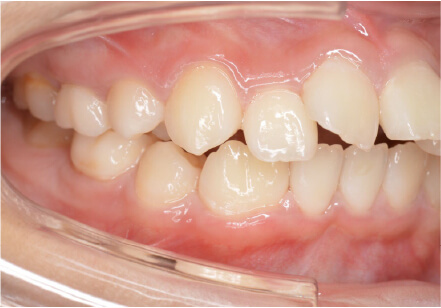

叢生の症例

8歳

女性

相談内容

前歯がでている、前歯が噛み合っていない

カウンセリング・診断結果

上下叢生、顎が狭いのでクリアコレクトで拡大配列+トレーニングで進めてく

治療内容・方法

全額アライナー矯正 クリアコレクト

術後の経過・現在の様子

リンガルアーチ使用

治療のリスク

痛み・歯根吸収・歯肉退縮・虫歯・後戻り

費用・治療期間

924,000円、8ヶ月